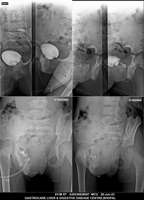

Section: URETHROGRAM Total: 95 images